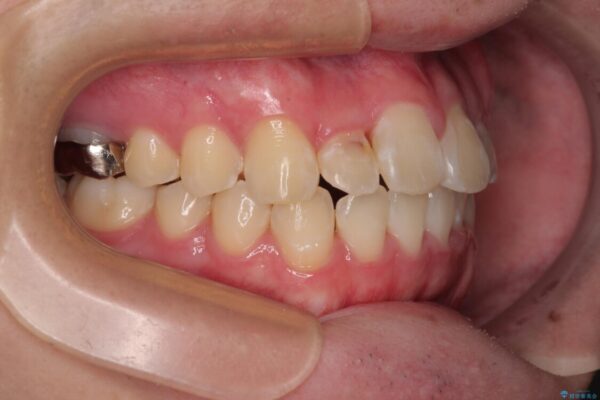

治療途中

• 1年でここまで変わる!歯列のがたつきと正中のズレを改善した矯正治療(メタルブラケット×MARPE) 治療途中画像

・上下ともに歯がきれいに並びきらず、がたつきが見られました。

・上下の前歯の中心(正中)がずれています。

・特に上顎の幅が狭いため、下顎の歯列も内側に入り込み、歯が並ぶスペースが不足していました。